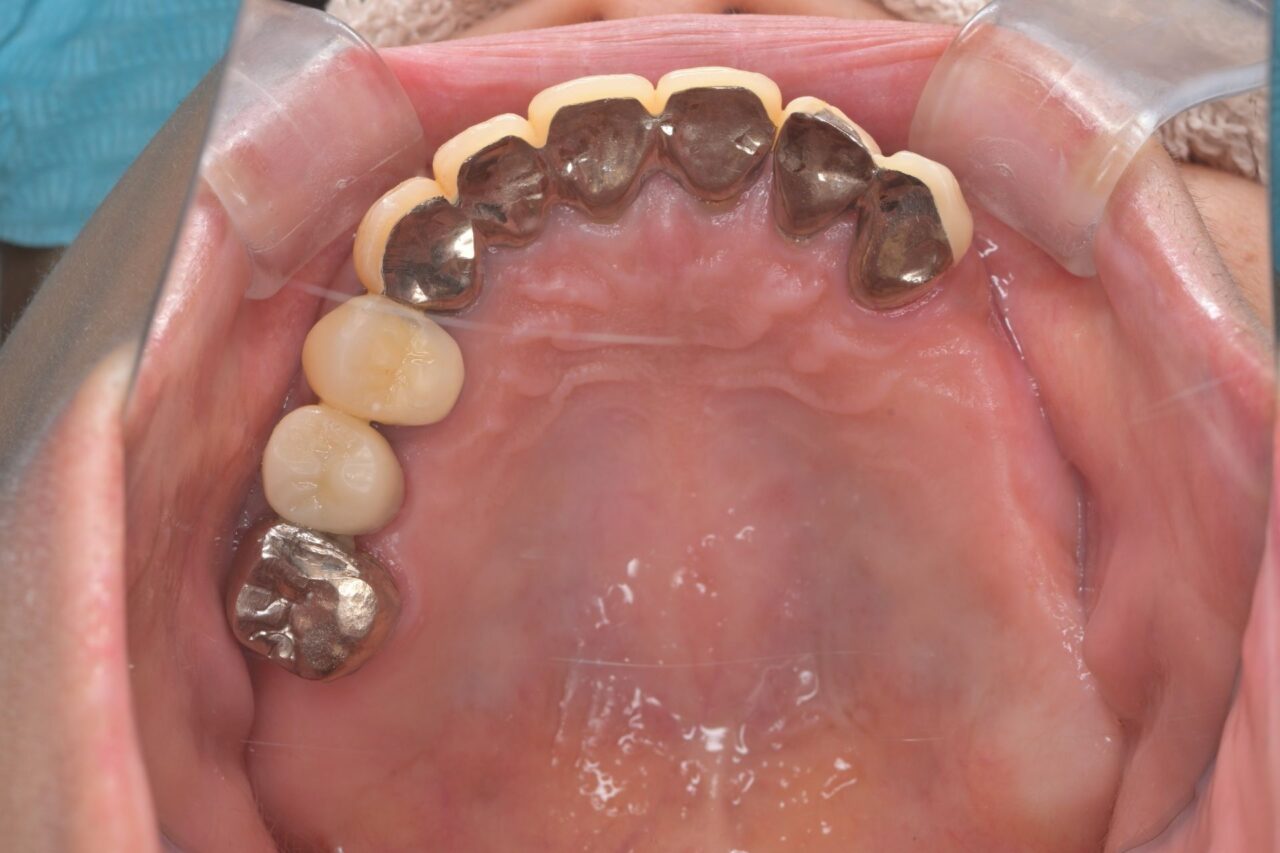

上面

歯が無い部分は入れ歯で補いました。

左右の入れ歯を金属でつないで強固にしています。はじめは舌感が悪いと思いますが、慣れが必要です。